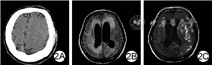

入院后1个月,患者在未使用镇静剂前提下仍昏睡,可唤醒、能遵医嘱完成少量动作,随后再次入睡,颅脑CT未见明显异常,此时未行颅脑磁共振检查;入院后3个月,患者半昏迷,对疼痛有反应,不能遵医嘱完成动作,颅脑磁共振检查示明显脑积水、脑水肿、出血灶、梗死灶;入院后4个月,复查颅脑磁共振示脑积水有所减少,仍存在脑水肿,并出现新软化灶、梗死灶、出血灶。见图2。